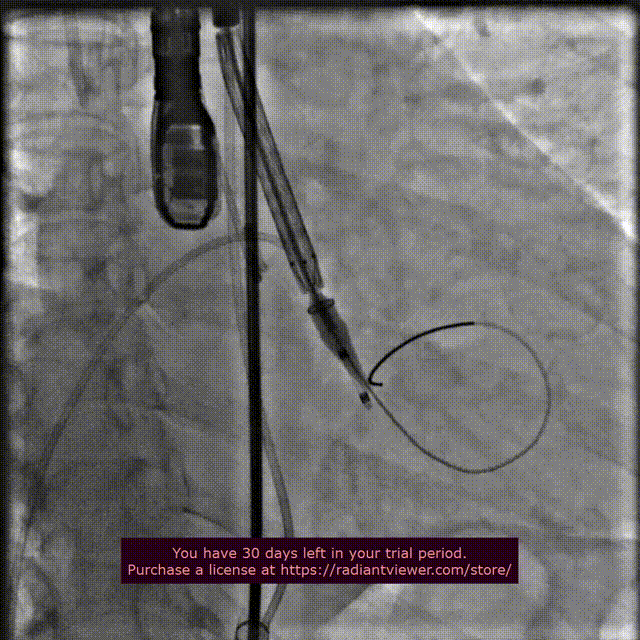

术者团队配合默契,送入输送系统至指定区域,根据术前规划的手术方案,选择于高位释放。在影像、超声的共同指引下,术者团队通过调整输送系统至最佳位置实现精准释放,一次释放取得成功。

瓣膜定位释放

瓣膜释放完毕后造影

患者脉压差即刻显著下降,再行主动脉造影提示瓣膜置入位置良好、形态完整,超声提示未见明显瓣周漏。术中及术后未出现相关并发症,圆满取得此次手术成功。